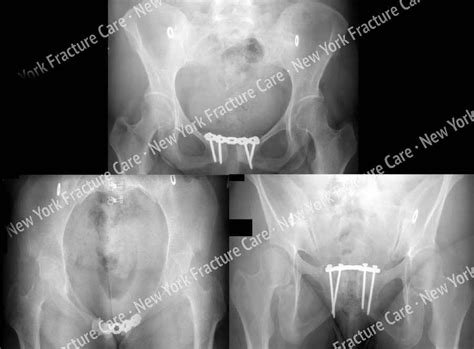

Types of pelvic floor injury during childbirth. A minor fracture is usually treated with bed rest and medication. This includes any break of the sacrum, hip bones (ischium, pubis, ilium), or tailbone. William smellie the female bony pelvis provides the infrastructure to support the pelvic organs and to allow childbirth. In this bulletin, more obvious reasons for pelvic floor dysfunction after childbirth are addressed but is it only lacerations and more easily recognizable injuries during childbirth that are causing the problem? The connection between pelvic floor dysfunction and childbirth is seemingly beyond debate. Clavicle fracture in a newborn during childbirth. This flexible joint is necessary for the pelvis to flex and expand during childbirth. But it can be painful. What is pelvic pain during pregnancy? A fractured coccyx can be quite painful and symptoms can take. Symptoms include pain, particularly with movement. Pelvic fractures can be seen in any group of patients. The first is based on the stability of the pelvis and. Ebraheim's educational animated video describes fracture injury conditions and treatment associated with the pelvis.stability of the pelvis. After all, ligaments are stretching, hormone levels are changing, and organs are levels of estrogen, progesterone, and relaxin (which helps your ligaments stretch for childbirth) rise during pregnancy. She was referred to to us for definitive care for pelvic injury and associated pain symptoms following childbirth.